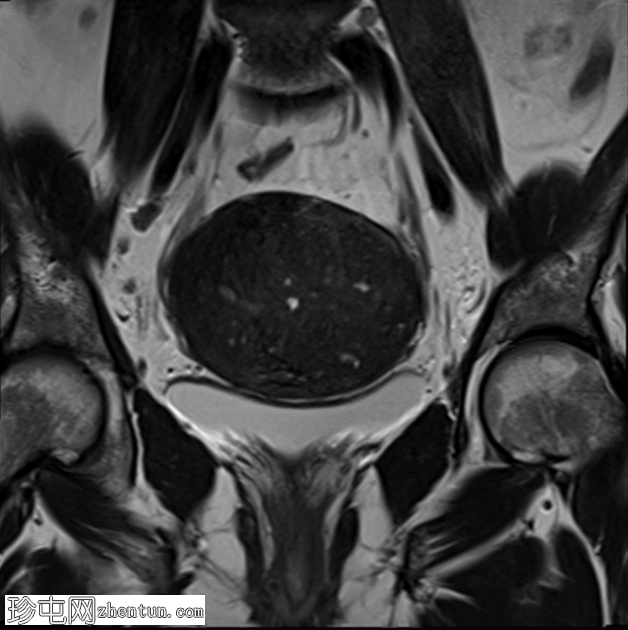

冠状位

T2加权像

子宫增大,交界区弥漫性增厚,厚度约2.5 cm,边界模糊,在T1加权像和T2加权像上均可见无数点状高信号灶,提示出血灶。